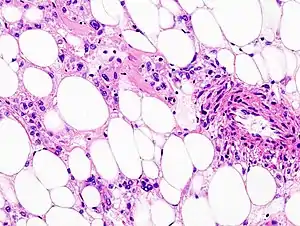

Histopathologic image of renal angiomyolipoma. Nephrectomy specimen. H&E stain.

PECs consist of perivascular epithelioid cells with a clear/granular cytoplasm and central round nucleus without prominent nucleoli.